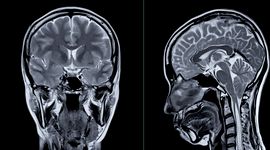

Creierul uman nu este un mecanism fix, ci un organ flexibil, care își schimbă constant structura. Cercetători de la Universitatea Cambridge (Anglia) și Universitatea din Pittsburgh (SUA) au identificat patru momente-cheie în evoluția conexiunilor cerebrale, de la naștere până la vârsta înaintată. Aceste schimbări apar în jurul vârstelor de 9, 32, 66 și 83 de ani, astfel creierul trece prin 5 „epoci”: copilăria, adolescența, maturitatea, îmbătrânirea timpurie și îmbătrânirea avansată.

De-a lungul vieții, creierul trece prin 5 „epoci”. Analiza RMN-urilor a peste 3.800 de persoane neurotipice, cu vârste cuprinse între câteva luni și 90 de ani, arată că arhitectura creierului suferă transformări majore în aceste momente.